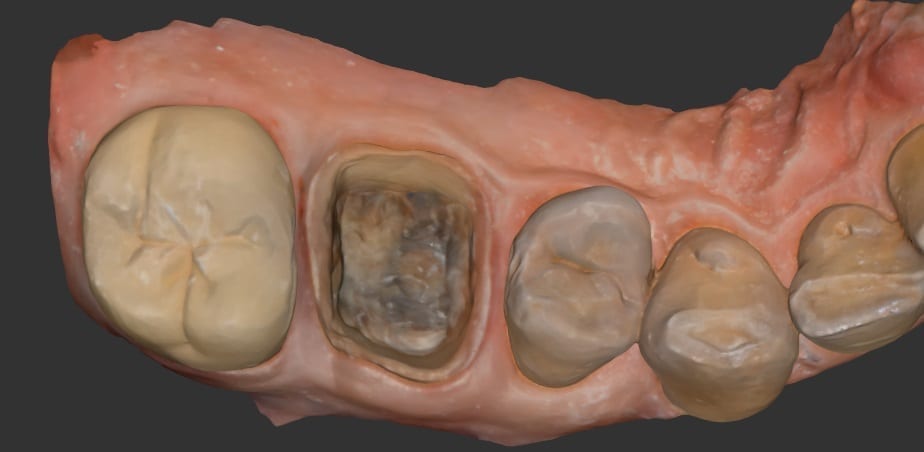

Powderless, Full Color Intraoral Scanning (IOS) Price and Specs Comparison Chart

July 21, 2018The prices and specifications cited in these charts are best estimates from published data readily available on the internet. We suggest you verify the numbers for accuracy and fluctuations over […]